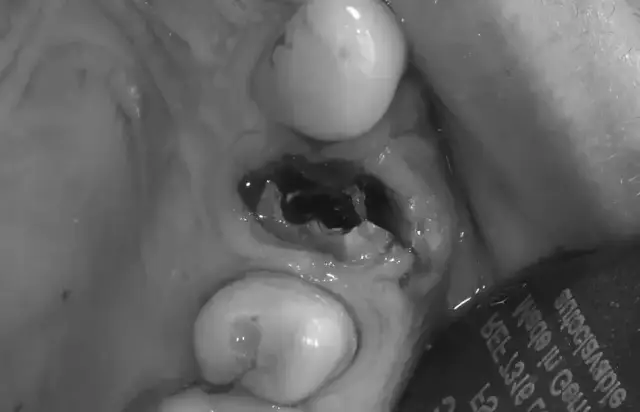

Dieta po ekstrakcji zęba to klucz do szybkiego gojenia. Sprawdź, co jeść i pić przez pierwsze dni, by uniknąć bólu, suchego zębodołu i powikłań.